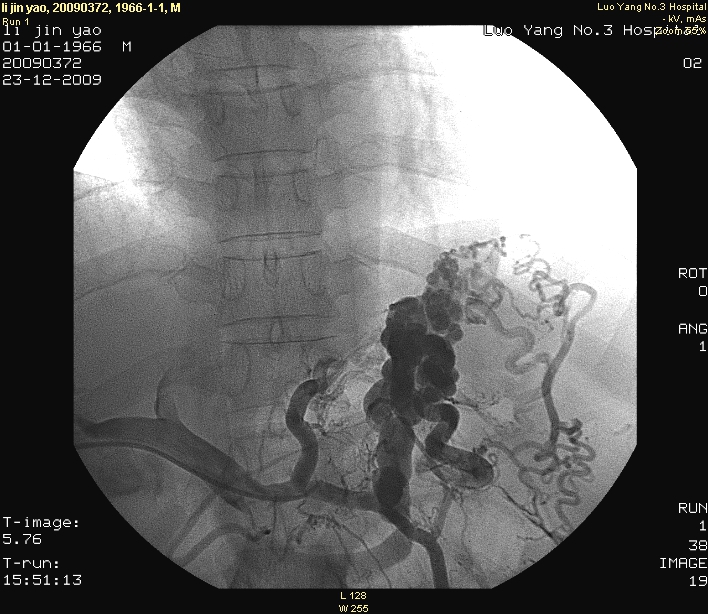

(七)、经皮经肝胃冠状静脉栓塞术

是消化内科开展的另一项治疗肝硬化并发消化道大出血的另一种血管介入技术,该技术通过经皮肤、经肝进入门静脉—胃冠状、胃短静脉—食管、胃底曲张静脉,注入栓塞剂(如无水酒精、弹簧圈),使曲张静脉闭塞,可有效防治出血,明显降低出血机率,疗效显著。可与内镜下曲张静脉套扎术、外科断流术综合运用,提高疗效。